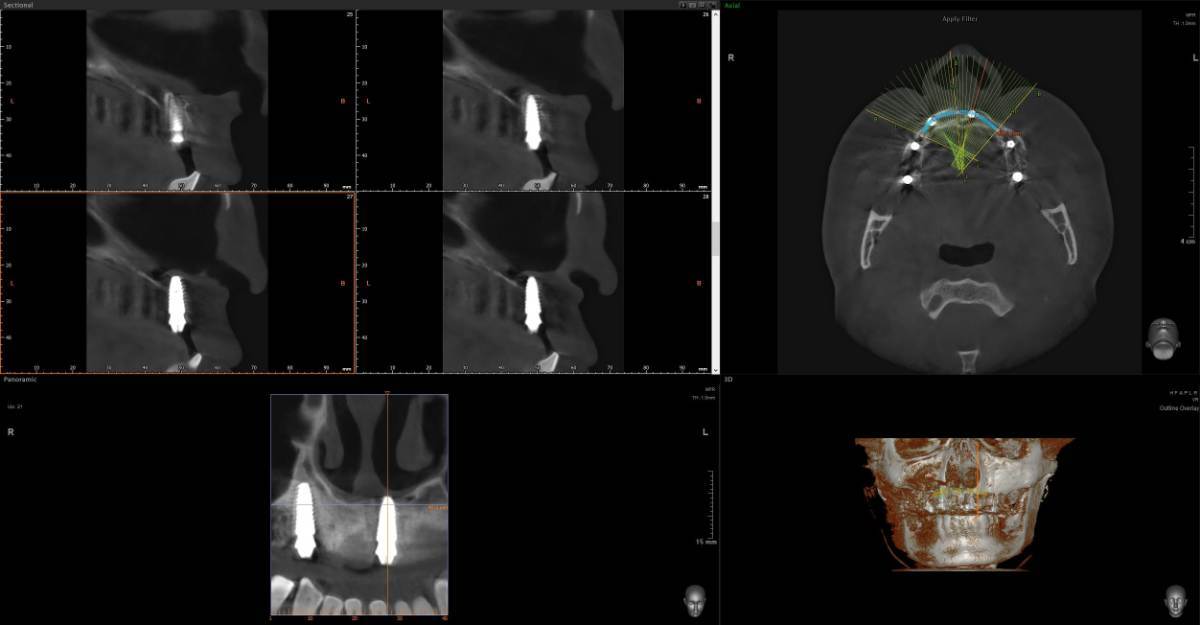

Всем привет, коллеги! 14 лет, терапевты ставят трещину по КТ (снимков до, к сожалению нет, косяк, каюсь). чуть сепарировав зуб и глянув на зуб под отлетевшим куском пломбы трещина "подтвердилась". Кейс на фото. Из интересного - маленький реколл в 1.5 года и спокойное перемещение зуба брекетами!

@сирена вот и завтра наступило) прощу прощения, что так долго, всё из головы вылетало на работе посмотреть. Пересадили в конце мая, к ортодонтии подключили в начале сентября ~3.5 месяца прошло с пересадки на тот момент.